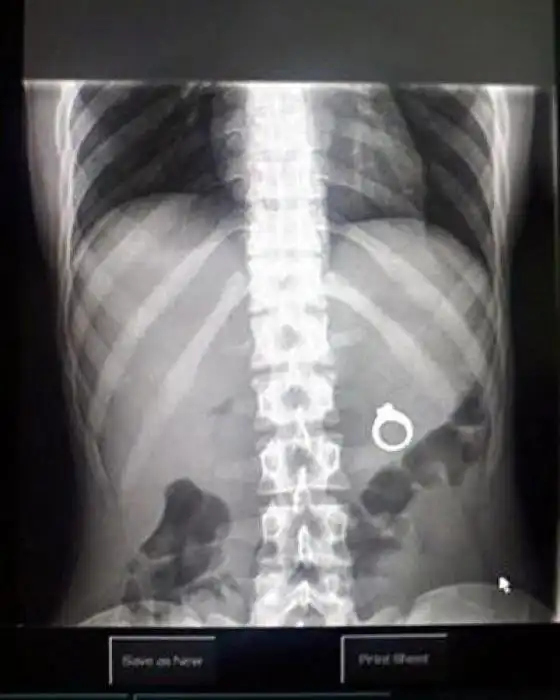

Необычные предметы в теле людей на рентгеновских снимках

На рентгеновских снимках людей порой можно обнаружить самые необычные предметы, которые находятся в их теле.